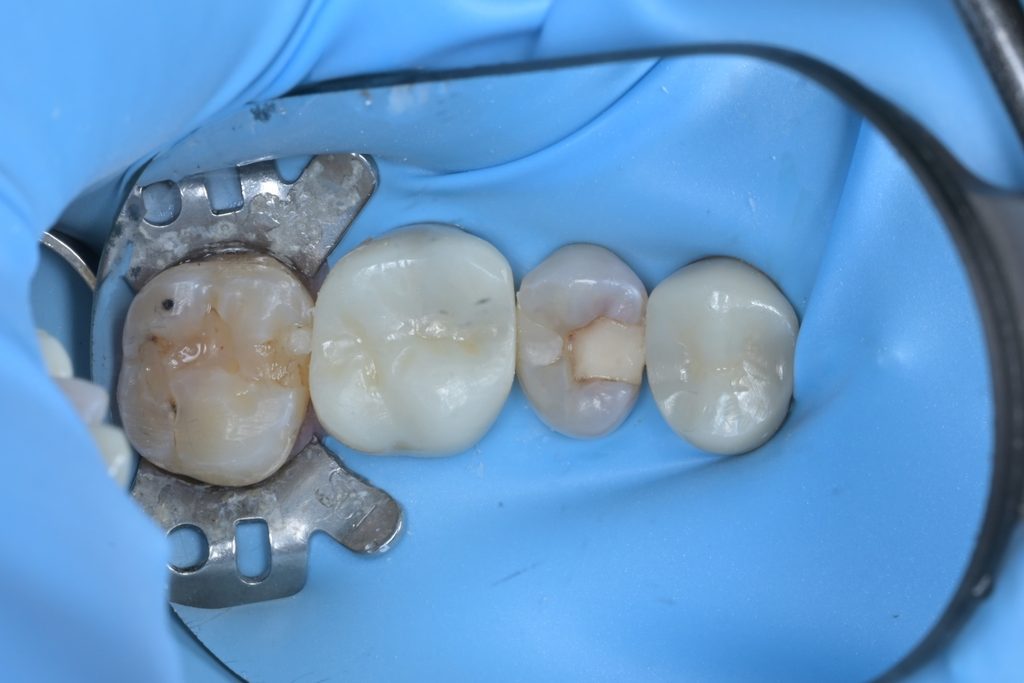

Step 1: 러버댐 격리

성공적인 치수 치료의 첫 단계는 완벽한 방습입니다. 치수가 침, 혈액, 세균에 오염되면 치료 성공률이 급격히 떨어지기 때문입니다.

Step 2: 우식 제거

미세현미경을 사용하여 기존 수복물과 우식 조직을 세밀하게 제거합니다. 우식검사액(Sable Seek)을 사용하여 남아있는 우식 조직을 염색하고, 건강한 치질만 남을 때까지 정밀하게 제거합니다.